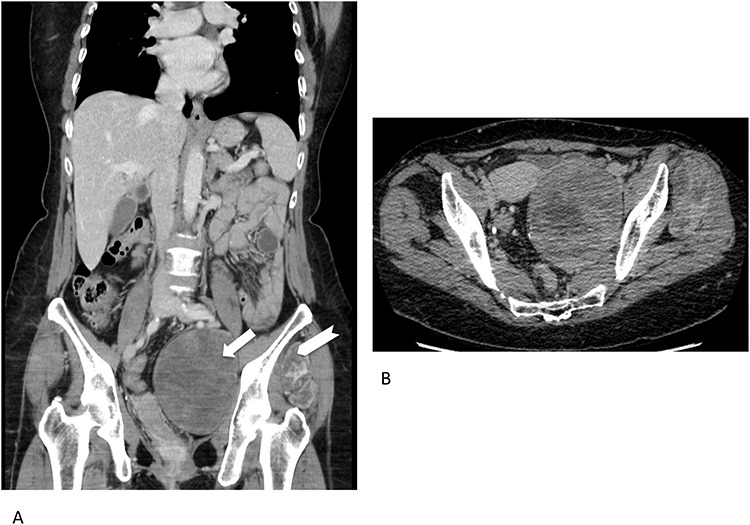

Concerning imaging description, the preliminary 64-raw MD-CT (Fig. 1) found a left-sided solid hypoattenuating, well-defined pelvic mass, with poor and inhomogeneous contrast enhancement. A similar mass coexisted in the intermuscular space between left gluteus medius and gluteus minimus.

Figure 1.

Multidetector computed tomography appearance of the lesions. Coronal multiplanar reformation (A) of the portal venous phase scan shows two different left-sided solid hypoattenuating masses located in the pelvis (arrow) and intermuscular space between the gluteus medius muscle and gluteus minimus muscle (arrowhaed). Progressive, slow and inhomogeneous contrast-enhancement occurred (B), as better appreciated in the transverse image acquired in the delayed phase.